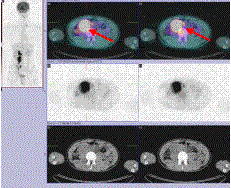

양전자방출단층촬영은 현재까지 고환암의 표준적인 영상진단방법은 아니지만 전이 병변에 대해 진단적 유용성이 있는 것으로 보고되고 있으며 특히, 치료 후 남아 있는 종괴에서 생존하는 악성 종양과 섬유화 또는 괴사 조직과의 감별 진단에 있어서 유용한 것으로 알려져 있습니다.

[CT에서 보이는 커져 있는 후복막림프절에 강한 신호강도가 확인되는 PET-CT scan소견]